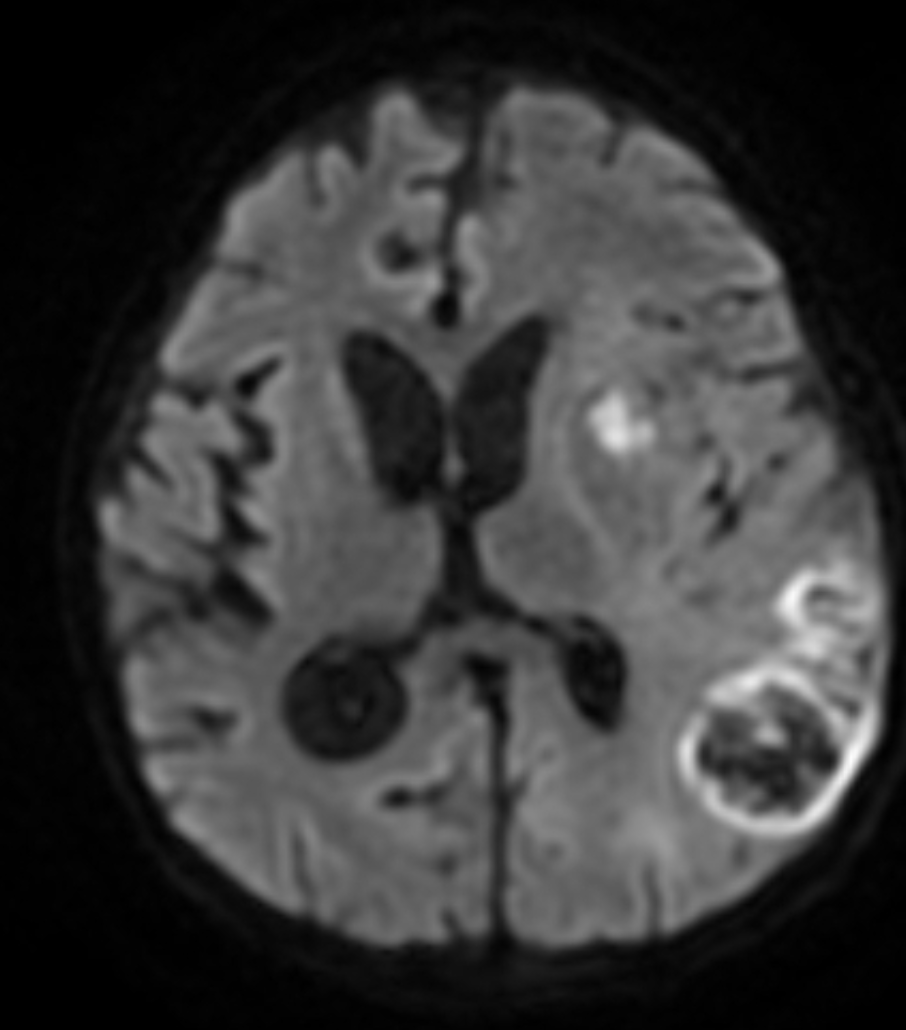

Note the multiple sites of oedema and haemorrhage, involving the brain stem and corpus callosum as well as subcortical white matter and left cerebral peduncle. High FLAIR signal is also seen in the dorsal midbrain. EVD insitu.

Case Discussion

Diffuse axonal injury can be subtle on CT but have devastating consequences for the patient. This is a case of grade III injury (involvement of brainstem) and carries a poor prognosis.

Diffuse axonal injury (DAI), also known as traumatic axonal injury (TAI), is a severe form of traumatic brain injury due to shearing forces. It is a potentially difficult diagnosis to make on imaging alone, especially on CT as the finding can be subtle, however, it has the potential to result in severe neurological impairment.

The diagnosis is best made on MRI where it is characterised by several small regions of susceptibility artifact at the grey-white matter junction, in the corpus callosum, and in more severe cases in the brainstem, surrounded by FLAIR hyperintensity.

Diffuse axonal injury is characterised by multiple focal lesions with a characteristic distribution: typically located at the grey-white matter junction, in the corpus callosum and in more severe cases in the brainstem (see: grading of diffuse axonal injury).

The appearance depends on whether or not the lesions are overtly haemorrhagic. Haemorrhagic lesions will be hyperdense and range in size from a few millimetres to a few centimetres in diameter. Non-haemorrhagic lesions are hypodense. They typically become more evident over the first few days as oedema develops around them. They may be associated with significant and disproportionate cerebral swelling.

CT is particularly insensitive to non-haemorrhagic lesions (as defined by CT) only able to detect 19% of such lesions, compared to 92% using T2 weighted imaging 4. When lesions are haemorrhagic, and especially when they are large, then CT is quite sensitive. As such, it is usually a safe assumption that if a couple of small haemorrhagic lesions are visible on CT, the degree of damage is much greater.

MRI is the modality of choice for assessing suspected diffuse axonal injury even in patients with entirely normal CT of the brain 5,6. MRI, especially SWI or GRE sequences, exquisitely sensitive to paramagnetic blood products may demonstrate small regions of susceptibility artefact at the grey-white matter junction, in the corpus callosum or the brain stem. Some lesions may be entirely non-haemorrhagic (even using high field strength SWI sequences). These will, however, be visible as regions of high FLAIR signal.